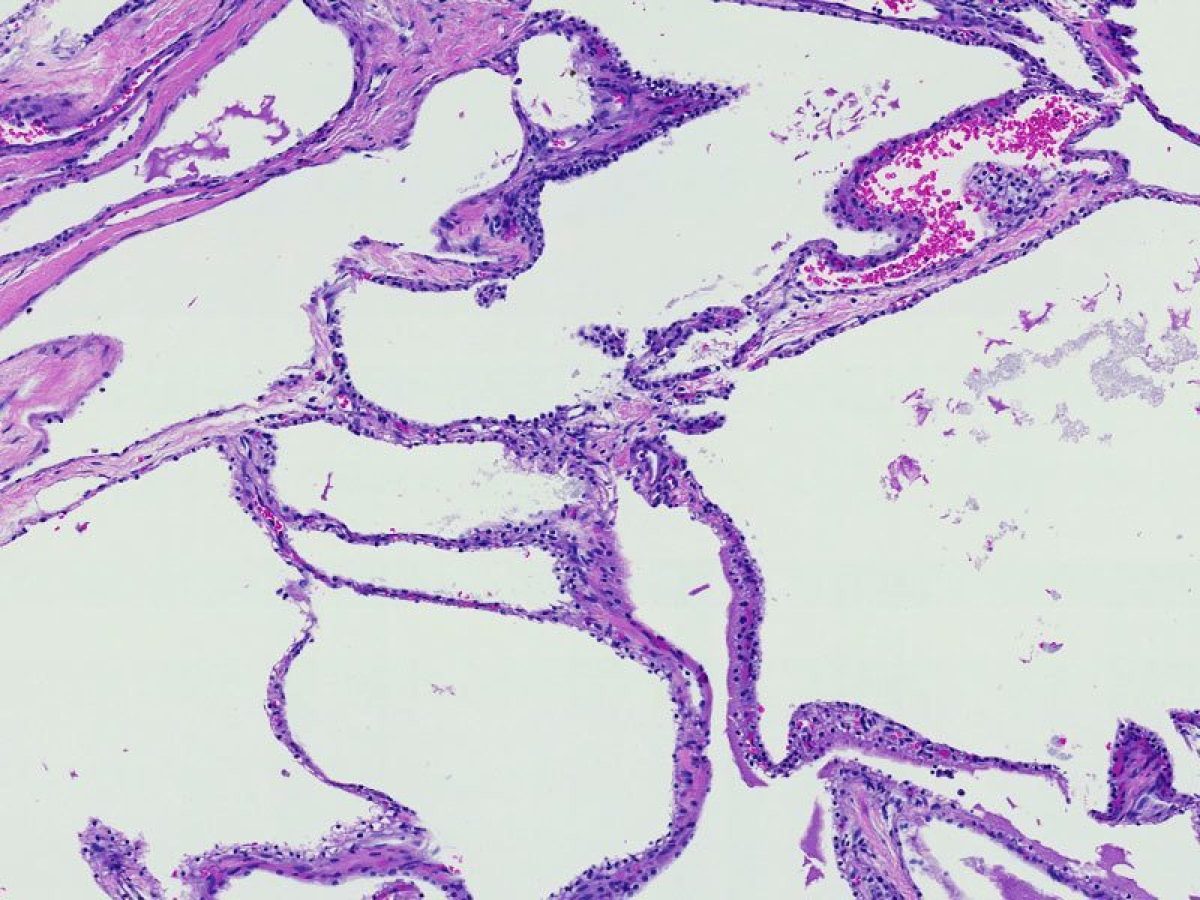

A term used to describe certain tumors which grow in finger-like projections. Pathologists use this term to describe some precancerous lesions in the pancreas (intraductal papillary mucinous neoplasm).